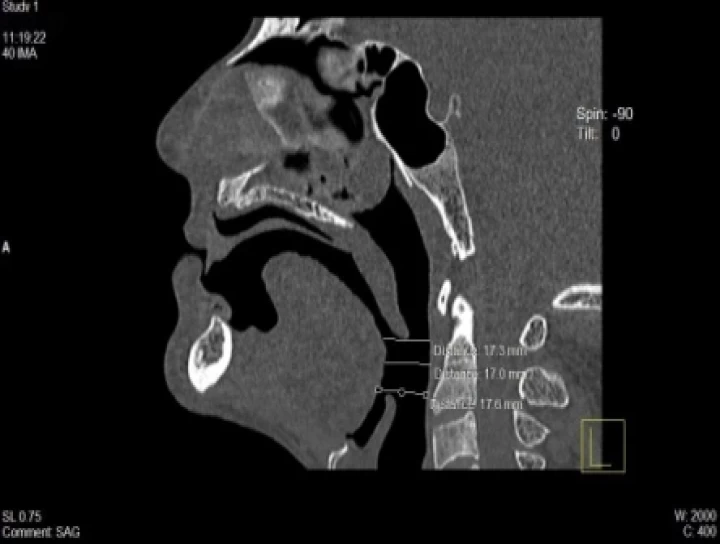

Purpose: This study was an attempt to verify the utility of complete dentures modified as a mandibular advancement device (MAD) in effecting expansio...